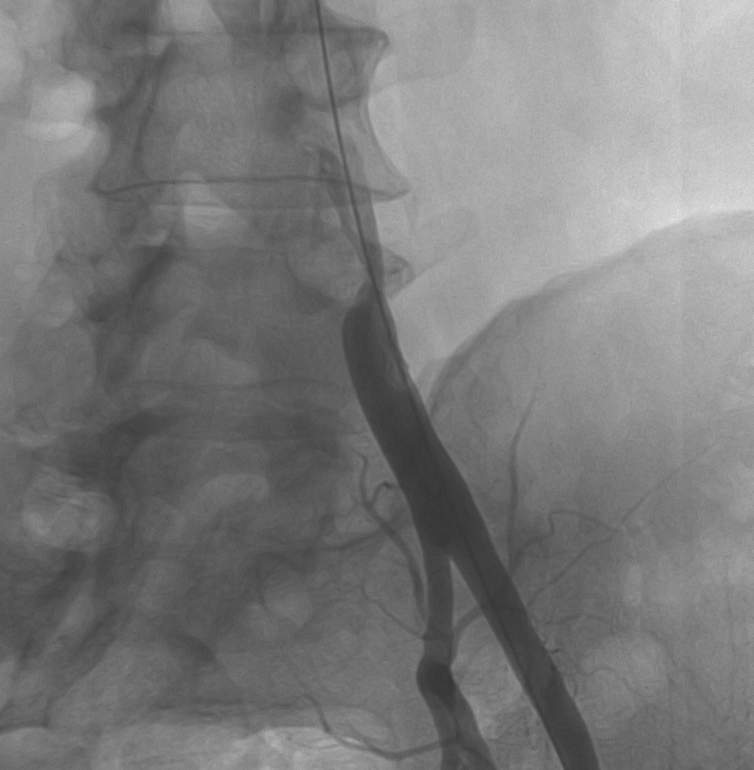

Due to technical reasons (antegrade or retrograde puncture, contralateral or ipsilateral puncture, femoral or brachial puncture), prognosis and risks, three types of levels are distinguished: iliac (Figure 4), femoro-popliteal (Figure 5) and crural (infragenual) (Figure 6) endovascular therapy. The latter two composes the infrainguinal group. PTA and stent placement are usually technically easier (with the exception of long occlusions), have a longer patency and carry lower risk in the iliac group compared to the other two groups. Patency following crural PTA is the worse and carries the highest risk, therefore, it is usually indicated only in Fontaine stages III and IV. The number of amputation per capita in Hungary is larger than that in most other European countries. In patients with gangrene and diabetes mellitus, crural PTA may save a large number of amputations. In case of successful PTA, limb salvage rate is considerably higher than crural patency rate, since perfusion needed for a healing ulcer or gangrene is considerably higher than for the basic functions (collateral arteries may be sufficient for such purpose). Subintimal PTA is performed more and more frequently: when luminal recanalisation is technically not possible, intentional dissection is done using the hydrophilic guidewire along the occluded segment; then, distally to the occlusion, the guidewire is directed back to the normal lumen and a new channel is formed along the normal lumen–dissected channel–normal lumen route (Figure 5).

Figure 5. Subintimal percutaneous transluminal angioplasty (PTA). Panel A: Superficial femoral artery has been occluded from its origin with a stump (upper arrow). Refilling occurs at the distal SFA (lower arrow), total length of the occlusion is approximately 18 cm. Panel B: The white background („roadmap”) shows the profunda femoral artery. The guidewire (in black on the white background; arrow) is at the beginning of the occluded segment. Panel C: the guidewire forms a loop (arrow), and gradually proceeds into the subintimal space. Panel D: the tip of the guidewire reached the normal popliteal artery lumen, there is no loop formation any longer. Panel E: Following balloon dilation of the whole segment, SFA shows quick flow in its entire length.